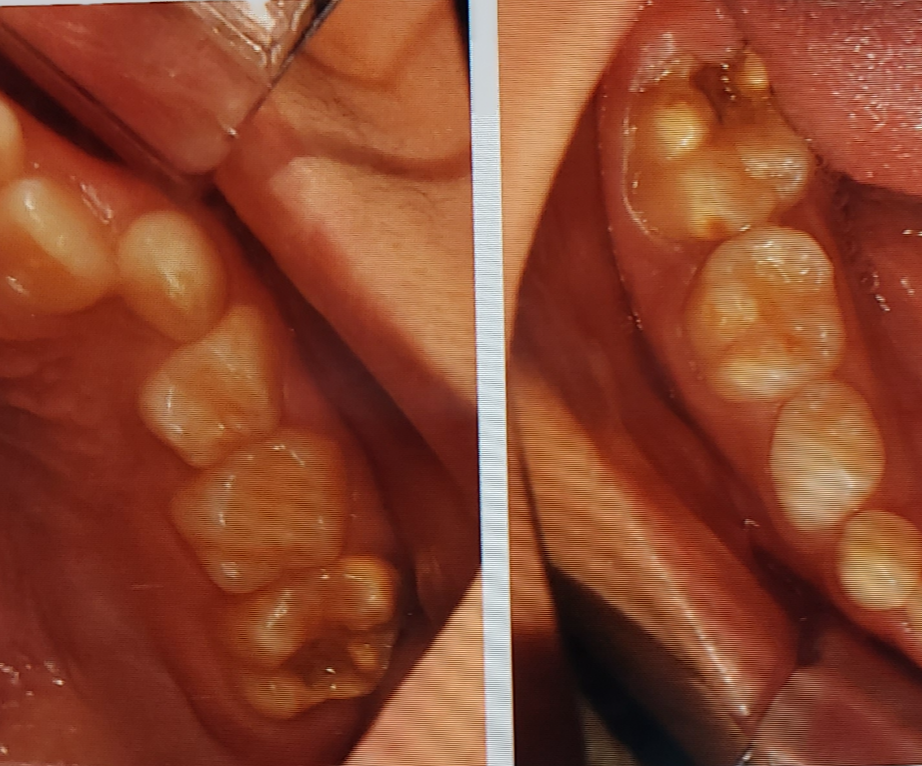

10살이 되면서 영구치 어금니가 올라왔습니다. 그런데 치아 색상이 조금 이상했습니다.

어린이 10명 중 1명(10%) 이상에서 나타난다는 치아의 저광화 현상은 다음과 같습니다.

치아의 한 개 혹은 다수의 제1대구치(첫번째 큰 영구치 어금니, 총4개)에 발생하는 법랑질

저성숙을 말합니다. 특히 제1대구치와 앞니는 비슷한 시기에 발육하기 때문에 제1대구치가

법랑질 저성숙을 보이는 경우 앞니에도 그 양상이 같이 나타날 수 있습니다.

이러한 저광화 치아의 특징은 다른 치아보다 크기가 작거나, 한 두개의 치아색이 다른 치아와 다르고

뜨겁거나 차가운 음식을 먹을 때 매우 민감하게 반응하거나 평소 양치질을 하며 시리다고 할 수 있습니다.

양치질을 안한것도 아닌데 위 아래 영구치 어금니에서 충치는 진행되고 있었습니다. 아니 처음 올라올 때부터

충치가 있는 상태로 올라온것 같기도 했습니다. 저광화 치아라는걸 몰랐을때는 관리를 안해준거 같아

첫 치료날 위에 어금니 신경치료없이 충치 제겨후 레진으로 치료가 끝났습니다. 치료시 웃음가스

위에 어금니 보다 충치 부위가 넓었던 아래 어금니는 일주일후 역시 같은 방법으로 충치제거후

레진으로 치료가 깔끔하게 끝났습니다. 모든 치과에서 신경을 절제하자 했으며 크라운으로 씌워야

부모 입장에는 어금니 2개모두 신경을 살렸고 레진으로 깔끔하게 치료가 되어 매우 만족스러웠습니다.